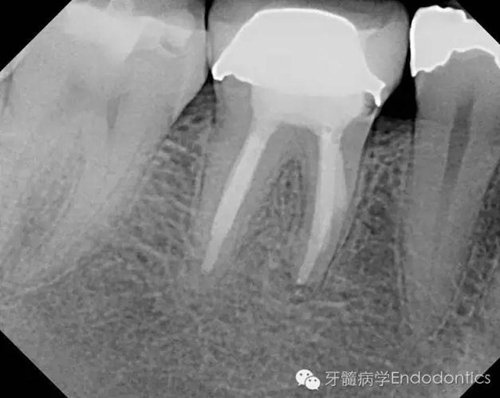

我決定對患牙行一次性根管再治療。我成功的取出了一根斷針和三根(其中兩根超出根尖)Thermofil(固核載體)。對所有根管進(jìn)行徹底的清理、成形,干燥后使用熱牙膠垂直加壓技術(shù)完成充填。

圖3.取出的斷針和固核載體